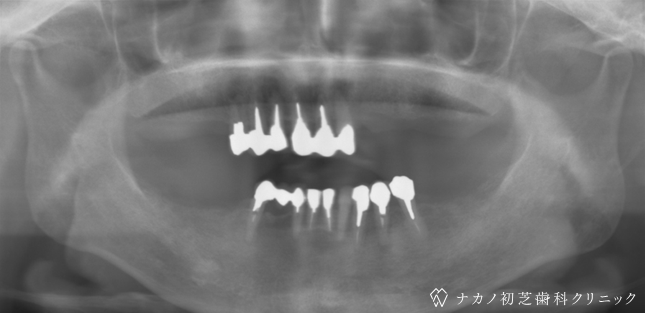

インプラント・13本 (60代女性)

-

BEFORE

AFTER

年齢 60代女性

治療内容 インプラント治療13本(骨造成の併用)

インプラント治療とは、歯を抜いた所にチタン製の人工歯根を埋入し、その上に歯を入れる方法です。骨を増やすことで、より審美的に治療が出来ました。費用 1本 400,000円(税込 440,000円)

リスク・副作用

腫れ・疼痛・違和感を感じるなどの症状を生じることがあります。